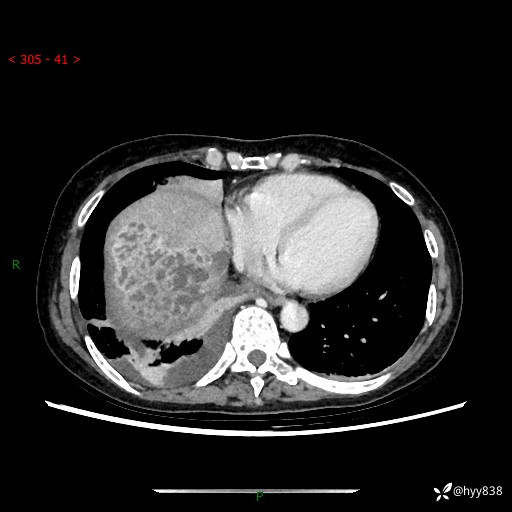

上腹部CT平扫